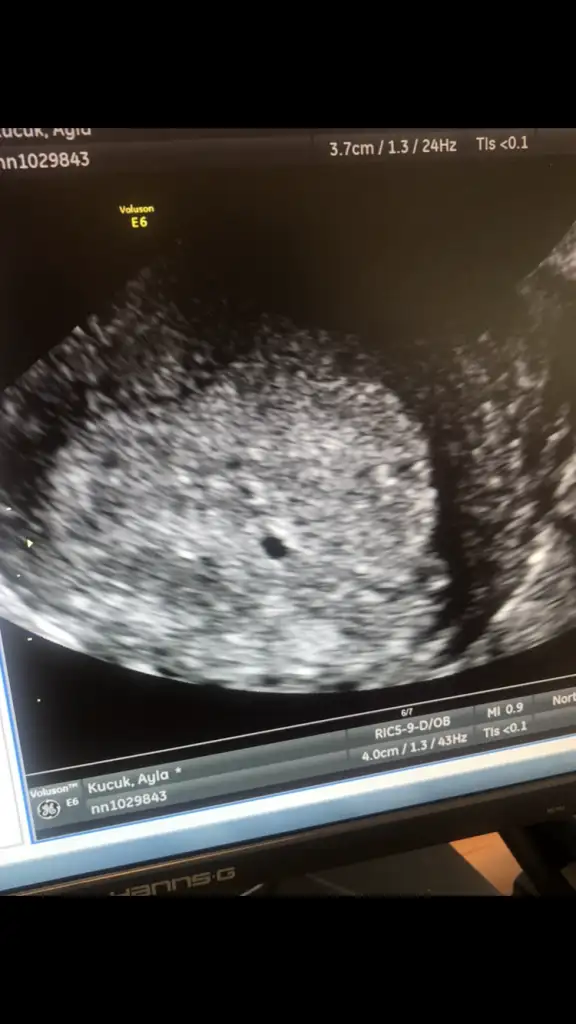

Bu hafta sali 1970 ctesi(bugun) 3200du. Doktor gecen haftadan beri iki uc gun arayla alttan ultrasonla bakiyordu goremiyordu. En son cuma gunu kucucuk bi kararti gormustu rahim icinde ama kese oldugundan emin olmamisti. Sali gunu biraz buyumustu bugunde cok azcik buyumustu o gordugu yapi. 5.8 *3 mm dedi. Onun hala kese oldugundan emin degil ve 3200le kesinlikle alttan net gorunmesi gerekiyodu dedi. Pteside goremezse dis gebelik teshisi kesinlesecek dis gebelik yasayan arkadaslar tecrubelerinizi yazabilirmisiniz?